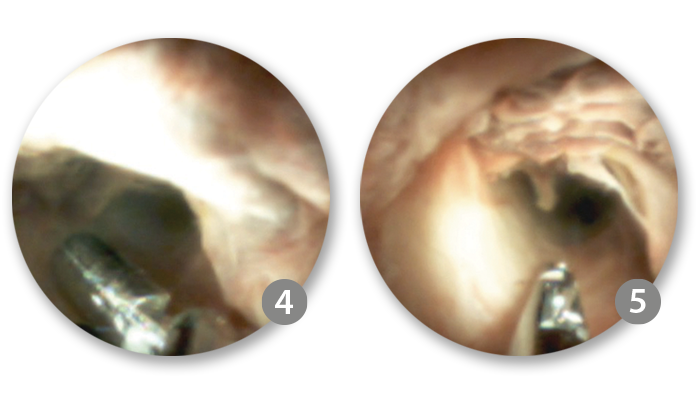

4. Targeted biopsy with SpyBite™ Max

The lesion extended from 3 mm below the cystic take-off, through the mid CBD and ended 4-5 mm above the ampullary insertion. Targeted biopsies of the biliary stricture were performed using SpyBite™ Max and frozen sections were prepared for pathology examination.

SpyBite™ Max Biopsy Forceps

SpyBite™ Max Biopsy Forceps has been shown to acquire more than 2x tissue in an average bite.1